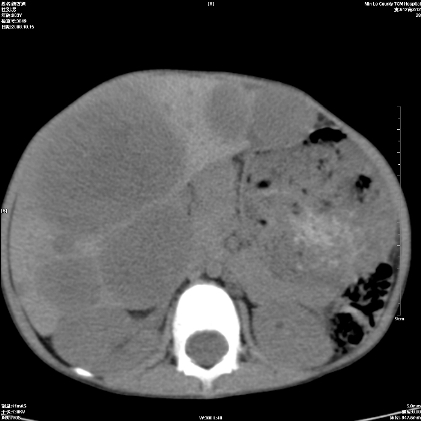

标题: PED1609:男性,3岁。彩超示肝Ca. [打印本页]

标题: PED1609:男性,3岁。彩超示肝Ca.

3岁;肝低密度灶;有钙化;有转移灶;考虑肝母细胞瘤;查afp

支持肝母细胞瘤肝内转移

考虑神经母细胞瘤并肝转移

考虑:1、右侧后下纵隔畸胎瘤。

2、肝脏多发血管内皮细胞瘤。

建议:增强确诊。